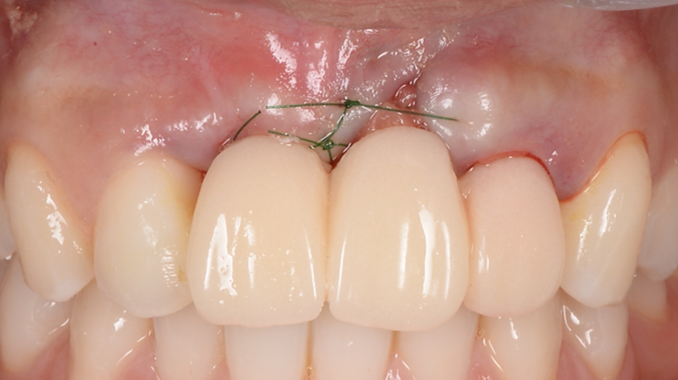

“AnyRidge is perfect for the anterior esthetic zone due to its strong initial stability & fast osseointegration.

Plus, KnifeThread® ensures space maintenance when using the PET/Socket Shield/Root Membrane Technique, showing excellent bone growth.”